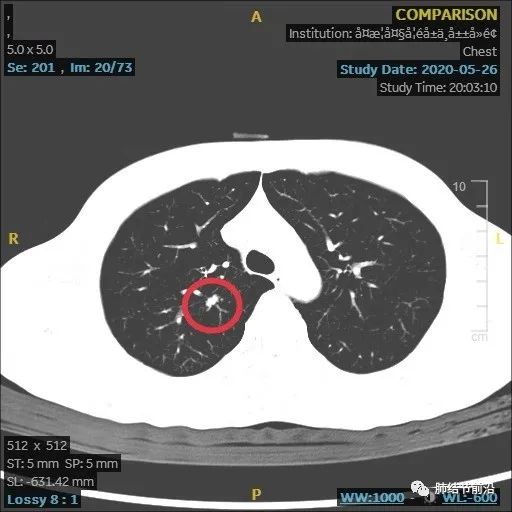

2020.5月首次发现。为8mm左右实性结节,查肿瘤指标等无异常发现,不除外肺癌。但当时无法确诊,建议患者随访。

6月后复查,结节发生变化(个人认为,8mm实性结节,首次建议3个月复查)。